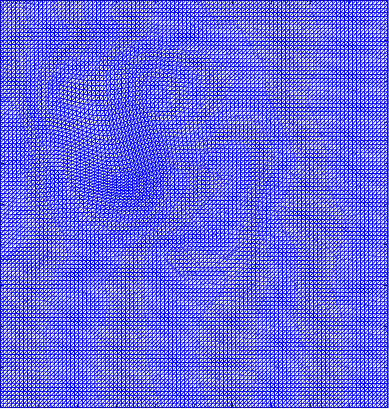

Figure 5 shows the ground truth and recovered maps of the registration maps in the last row of Table 4. It can be seen that ground truth low-rank mapping shown in Figure 5(a) resembles the recovered low-rank mapping shown in Figure 5(c). This again shows that we could obtain a meaningful mapping from the decomposition.

Figure 6 displays the 4 mappings as in Example 3 and 4. Again, we can see that after the decomposition of the Beltrami descriptor, the decpmposed mappings to large extent resemble the corresponding ones.